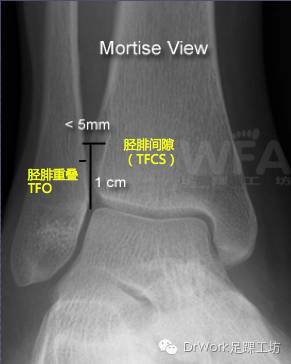

踝穴位片

• TFCS<5mm

• TFO>1mm

下胫腓间隙增加(TFCS)是其中最有效指标

• 投射角度外旋5o至内旋25oTFCS均无明显变化----适合诊断